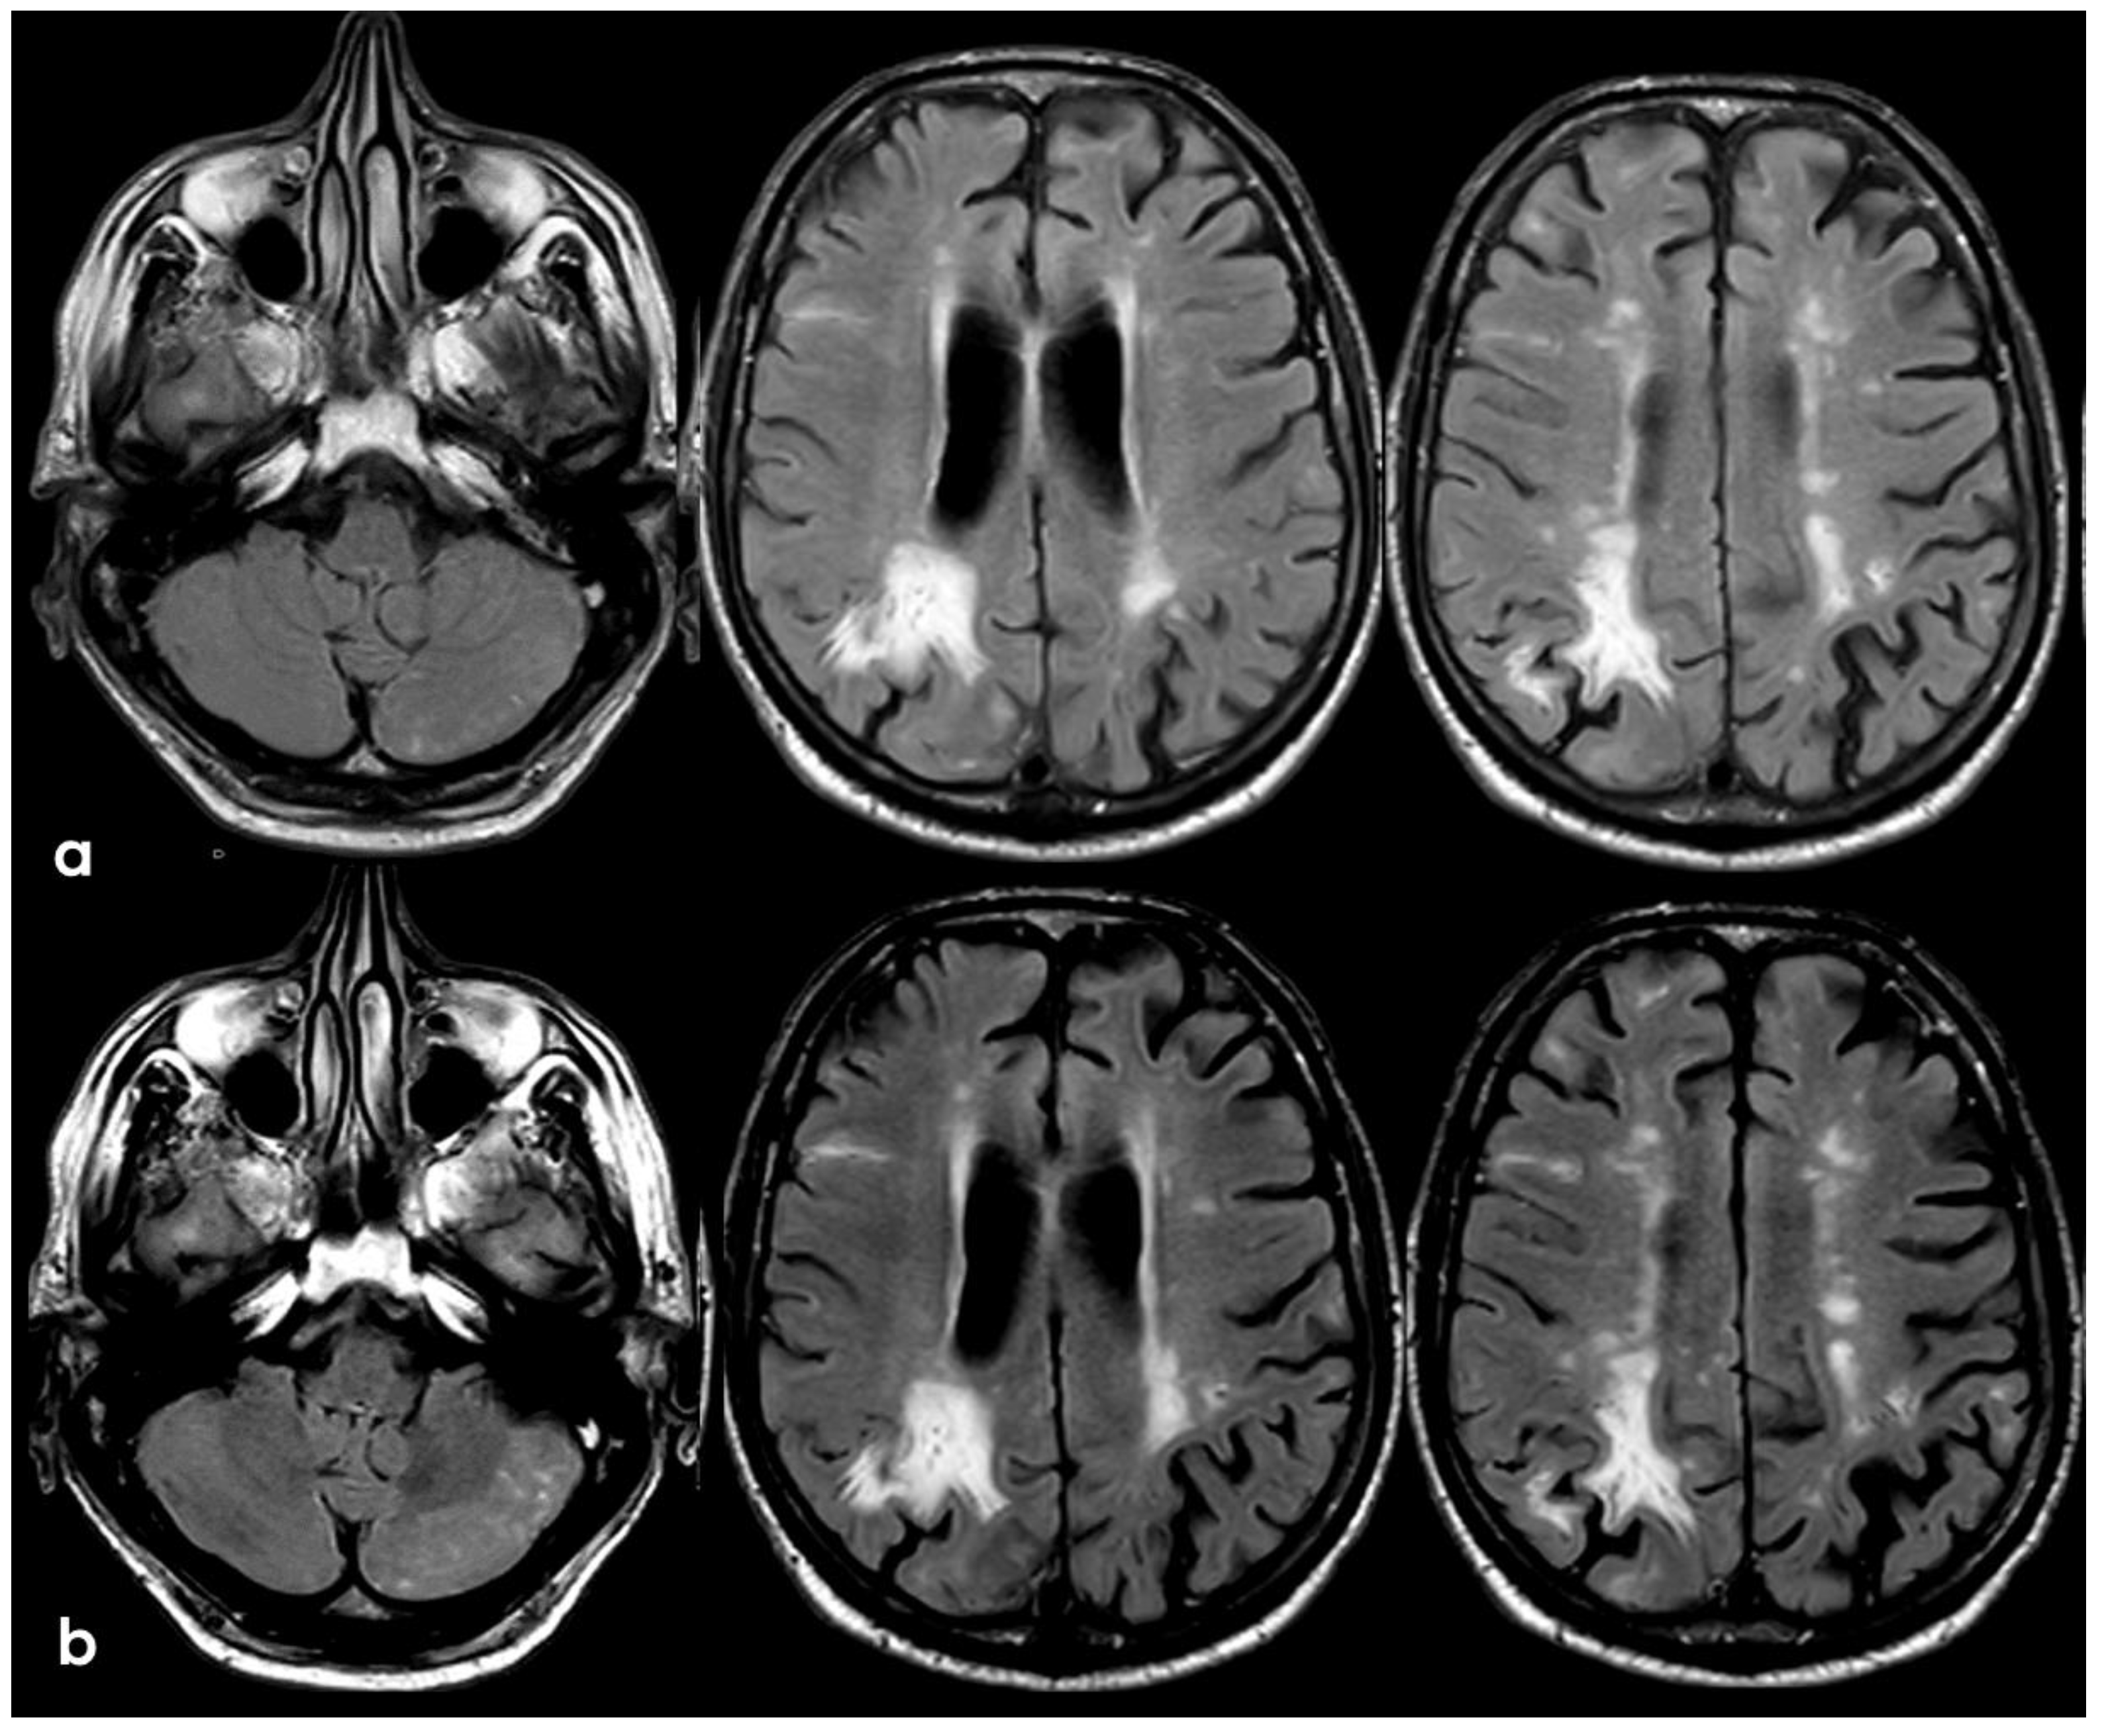

3. May 2014: CAA-Related Inflammation

5. February 2017: First Recurrent CAA-Related Inflammation